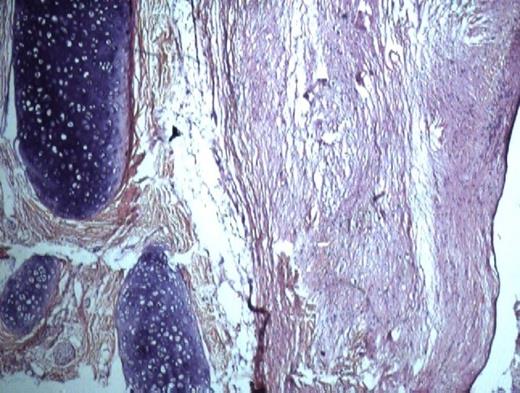

A 56 years old female presented with swelling on the dorsal surface of tongue. Examination revealed a firm, rubbery, non-tender 3x2x2cm sessile swelling with no induration or ulceration (fig 1).

She noticed this swelling 6 months previously, which more recently increased in size. Lately, she experienced difficulty in moving tongue, resulting in globbus sensation and dysphagia. General examination of the patient revealed average built, pulse rate 80 beats/min with regular rhythm, BP 130/90 mm Hg, RR 24 breaths/min. There was no history of fever, night sweats and weight loss. Jaundice, cyanosis and oedema were absent. Computed tomography revealed a 3x2 cm cystic anterior lingual structure, the wall of which was thin and regular with a content consisting of homogenous fluid. There was no bone involvement. With a clinical diagnosis of dermoid cyst an excision biopsy was performed. Histopathological findings consisted of cyst wall lining of stratified squamous epithelium with sebaceous glands, blood vessels, muscle and cartilage in the underlying connective tissue, and a diagnosis of teratoma was made (fig 2). No evidence of malignant transformation was noted. One year after surgical removal of the lesion, there was no sign of recurrence.